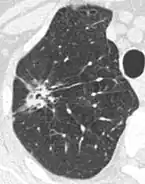

• Margin morphology: a spiculated margin is a risk factor for cancer.[8] Benign causes tend to have a well defined border, whereas lobulated lesions or those with an irregular margin extending into the neighbouring tissue tend to be malignant.[10] In particular, spiculations are highly predictive of malignancy with a positive predictive value up to 90%.[9] Also, a "notch sign", which is an abrupt indentation of the nodule, increases the risk of cancer, but may also be found in granulomatous diseases.[9]

• Pleural retraction is far more common in cancers.[9] It is the pulling of visceral pleura towards the nodule.[9]

Thin slice and maximal intensity projection of a lung nodule, the latter better visualizing vascular convergence.[9]

• Vascular convergence is where vessels converge to a nodule without adjoining or contacting the edge of the nodule, and is mainly seen in peripheral subsolid lung cancers.[9] It reflects angiogenesis.[9]